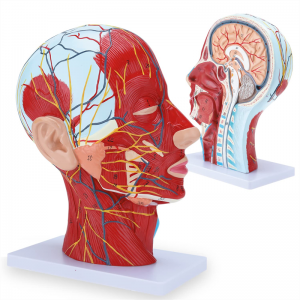

| Características | O modelo mostra a morfologia local dos lados interno e externo da seção sagital mediana da cabeça e pescoço, bem como as estruturas dos vasos sanguíneos e nervos, e há 84 partes indicando sinais no total. |

【Modelo superficial do músculo neurovascular】 Números altamente detalhados, marcados e destacáveis, aprofundar o entendimento dos músculos superficiais, vasos, nervos e as estruturas internas da cabeça e pescoço. Artéria vermelha, azul-veia, nervo amarelo.

【Apresenta】 mostra os músculos superficiais da face exposta; os vasos sanguíneos superficiais e os nervos do rosto e do couro cabeludo; as estruturas internas da glândula parótida e do trato respiratório superior; A estrutura de seção transversal sagital da coluna cervical.

Este modelo mostra detalhes do pescoço da cabeça direita e da seção sagital média do humano. incluindo o superficial

músculos da face exposta; os vasos sanguíneos superficiais e os nervos do rosto e do couro cabeludo; as estruturas internas

da glândula parótida e trato respiratório superior; A estrutura de seção transversal sagital da coluna cervical.

O modelo mostrou a morfologia local das seções sagitais mediais e laterais da cabeça e pescoço e suas estruturas vasculares e nervosas, com um total de 100 indicadores do local.

Este modelo é um modelo muscular neurovascular superficial grande e pescoço natural, um componente 1, mostrando os detalhes da cabeça e pescoço direito humano e seção sagital mediana, incluindo os músculos superficiais expostos da face, vasos superficiais do rosto e do couro cabeludo, nervos e a estrutura medial da glândula parótida e do trato respiratório superior, e a estrutura da seção sagital da coluna cervical